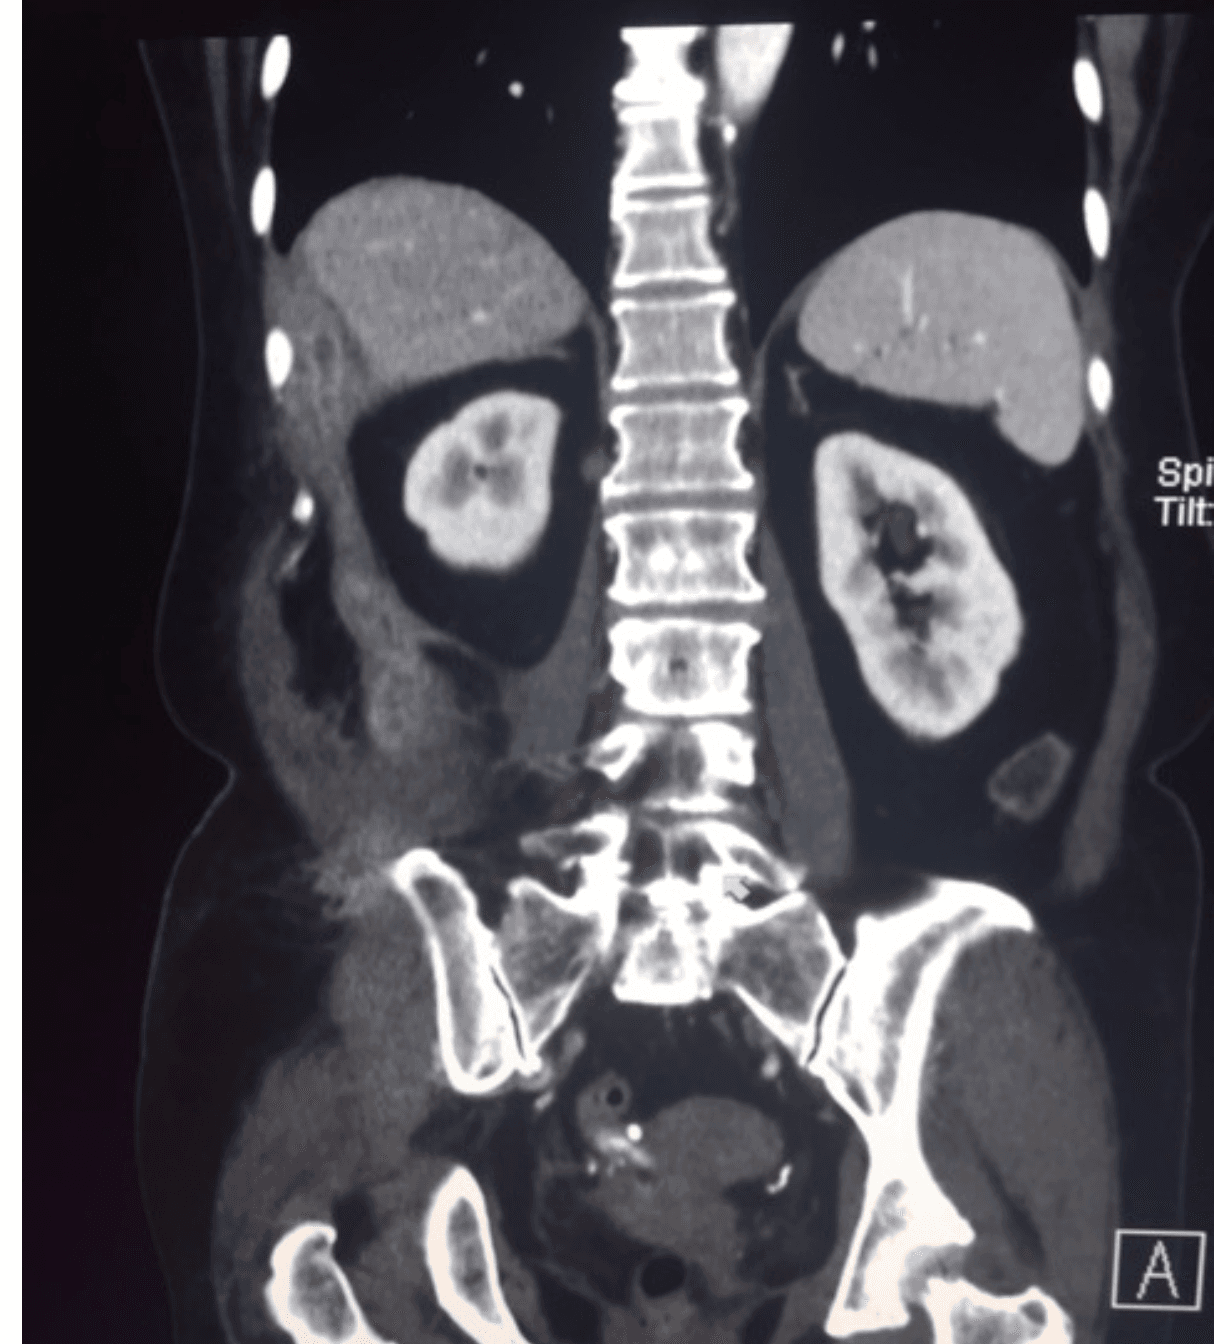

CT and tissue pathology were obtained because malignancy was initially suspected. Imaging showed an infiltrative soft-tissue process with mass-like appearance. Histopathology demonstrated sulfur granules with branching filamentous gram-positive organisms, consistent with actinomycotic infection.